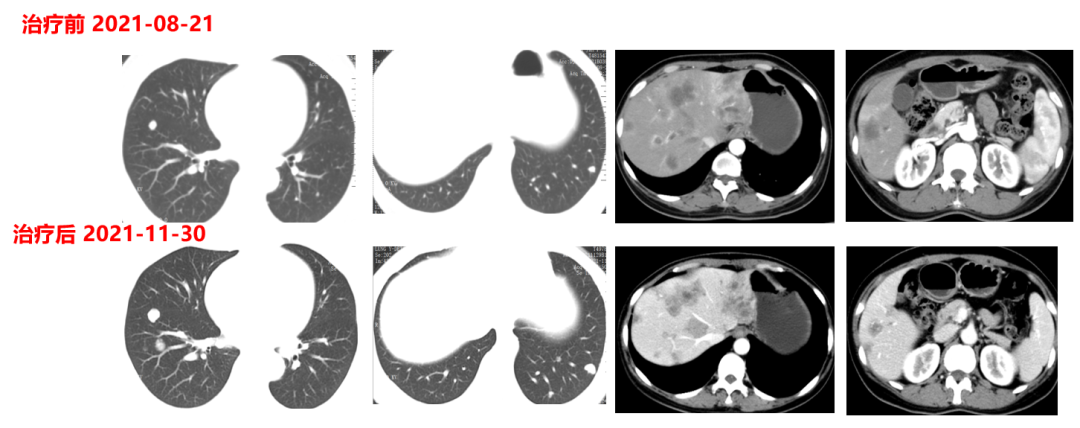

于2021.04.17行“FOLFOX6”方案化疗1周期,行“奥沙利铂”化疗时,出现严重过敏。因患者基因状态为RAS,BRAF野生型,第2周期始给予“FOLFIRI+西妥昔单抗”,在治疗过程中,肿瘤标志物持续下降,影像学也显示肝脏病灶明显缩小。疗效评价PR,在2021-09-25在局麻DSA下行“肝动脉造影并化疗灌注栓塞术”。

肿瘤初次进展(2021-11-30)

患者于2021年11月30号复查时,肺上病灶增大增多,肝脏病灶稍增大,肿瘤标志物增高,整体疗效评价PD,考虑一线治疗进展。

二线治疗(2021-12至2022-8-3,二线PFS:7月余):

于2021-12-03、2021-12-27给予伊尼妥单抗+吡咯替尼方案治疗2周期。2022.1.19始给予患者伊尼妥单抗+吡咯替尼+替雷利珠单抗治疗,两周期,四周期时的疗效评估可以看到,肺上病灶明显缩小,甚至有的病灶消失,肿瘤标志物也在持续下降。